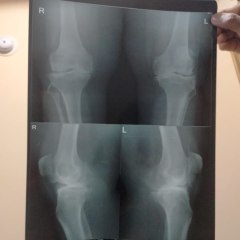

Prolozone Therapy